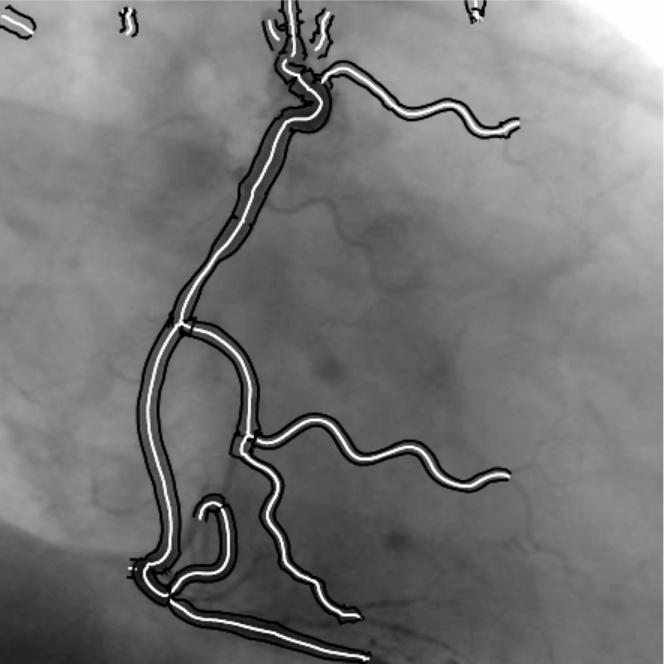

航空地图道路提取案例:

血管提取案例:

以上插图均来自 Steger 论文[1],脊线检测算法中最为广泛流传的就是这位大佬的算法。